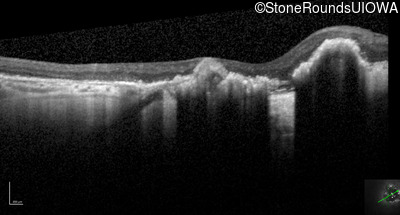

Optical Coherence Tomography - Left - Count Fingers 2'

Exemplar / OCT Stack